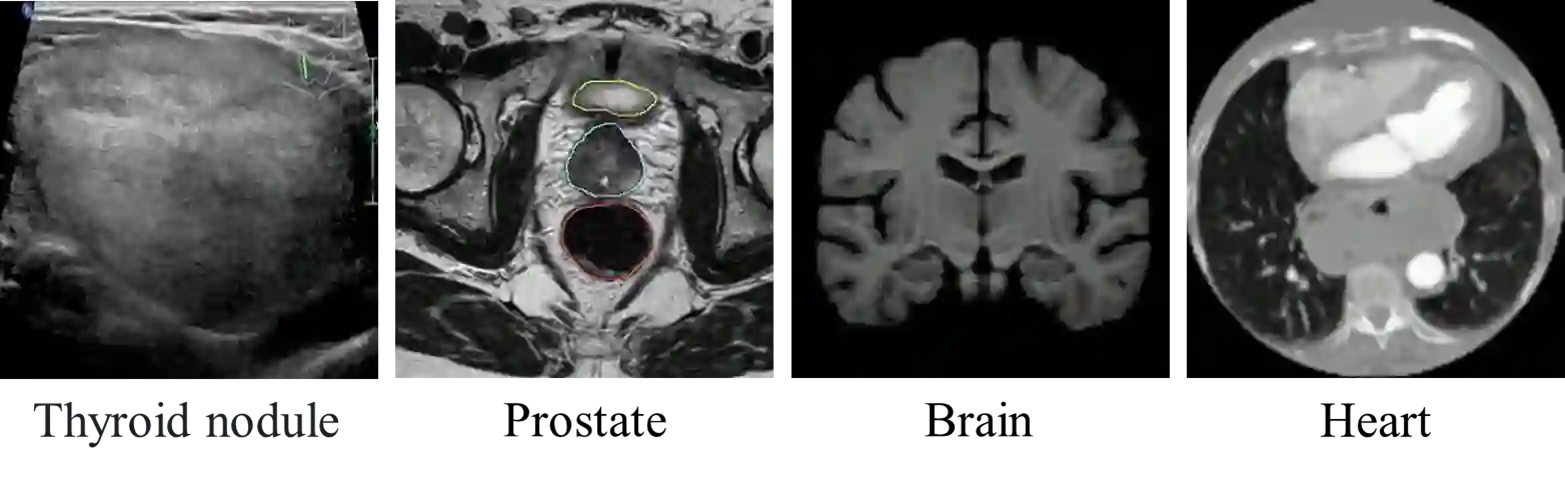

Segmentation of nodules in thyroid ultrasound imaging plays a crucial role in the detection and treatment of thyroid cancer. However, owing to the diversity of scanner vendors and imaging protocols in different hospitals, the automatic segmentation model, which has already demonstrated expert-level accuracy in the field of medical image segmentation, finds its accuracy reduced as the result of its weak generalization performance when being applied in clinically realistic environments. To address this issue, the present paper proposes ASTN, a framework for thyroid nodule segmentation achieved through a new type co-registration network. By extracting latent semantic information from the atlas and target images and utilizing in-depth features to accomplish the co-registration of nodules in thyroid ultrasound images, this framework can ensure the integrity of anatomical structure and reduce the impact on segmentation as the result of overall differences in image caused by different devices. In addition, this paper also provides an atlas selection algorithm to mitigate the difficulty of co-registration. As shown by the evaluation results collected from the datasets of different devices, thanks to the method we proposed, the model generalization has been greatly improved while maintaining a high level of segmentation accuracy.